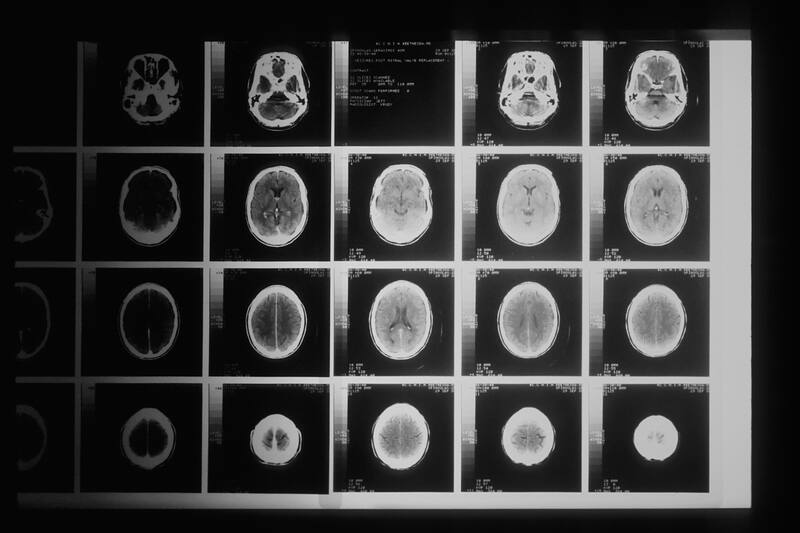

Dentro de nuestro cerebro, pequeñas áreas empiezan a interconectarse y activarse para sentir placer. El experto aseguró que en los experimentos, utilizan neuroimágenes para poder comprenderlo: “Eso nos ha permitido entender que se activan las mismas zonas, aunque sean distintos tipos de placeres”.